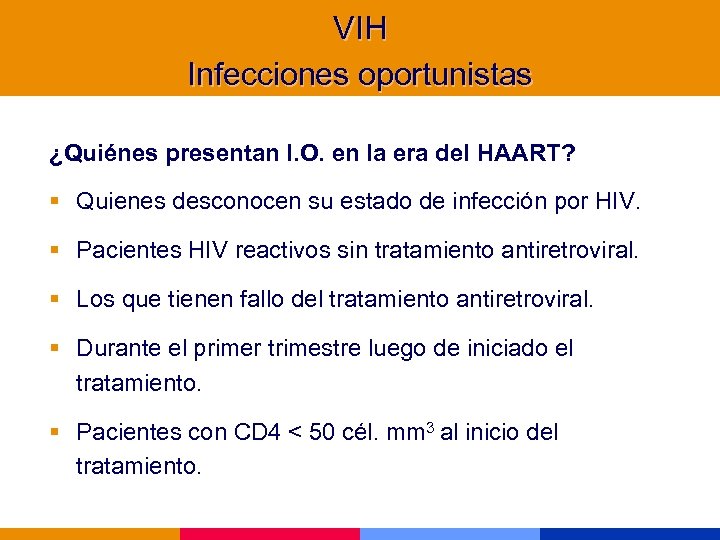

VIH Infecciones oportunistas ¿Quiénes presentan I. O. en la era del HAART? § Quienes desconocen su estado de infección por HIV. § Pacientes HIV reactivos sin tratamiento antiretroviral. § Los que tienen fallo del tratamiento antiretroviral. § Durante el primer trimestre luego de iniciado el tratamiento. § Pacientes con CD 4 < 50 cél. mm 3 al inicio del tratamiento.

VIH Infecciones oportunistas ¿Quiénes presentan I. O. en la era del HAART? § Quienes desconocen su estado de infección por HIV. § Pacientes HIV reactivos sin tratamiento antiretroviral. § Los que tienen fallo del tratamiento antiretroviral. § Durante el primer trimestre luego de iniciado el tratamiento. § Pacientes con CD 4 < 50 cél. mm 3 al inicio del tratamiento.